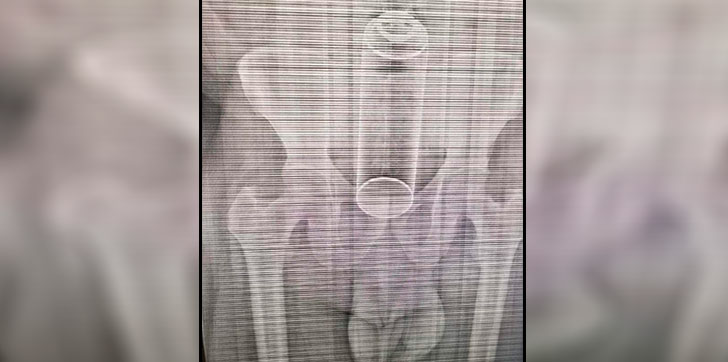

AGENDA56, SANTO DOMINGO.- Un hombre fue intervenido quirúrgicamente la mañana de este miércoles luego de que se le alojara un frasco de insecticida en el recto mientras sostenía relaciones sexuales con su pareja.

El hombre, de 40 años, llegó al hospital Moscoso Puello con el objeto alojado en el recto, según informó el relacionista del centro asistencial, Hanobi Delgado.